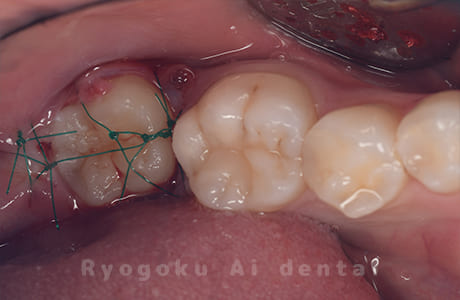

Case04

- 慢性根尖性歯周炎

- 治療内容

-

- 220,000円

他院で抜歯し、インプラントを進められた患者さんです。親知らずが残っていたため、移植治療がベストと判断し、治療を行いました。

<リスク・副作用>